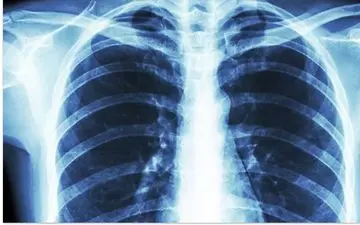

با همه گیری کووید ۱۹ در جهان، تشخیص ابتلا به سرطان ریه و یا ویروس کرونا به یک چالش برای کادر درمانی تبدیل شده است.

فوق تخصص ریه گفت: بیماری که دچار سرفه، بدن درد، ضعف، تب، اختلال بویایی و چشایی شده است، به احتمال زیاد به کرونا مبتلا…